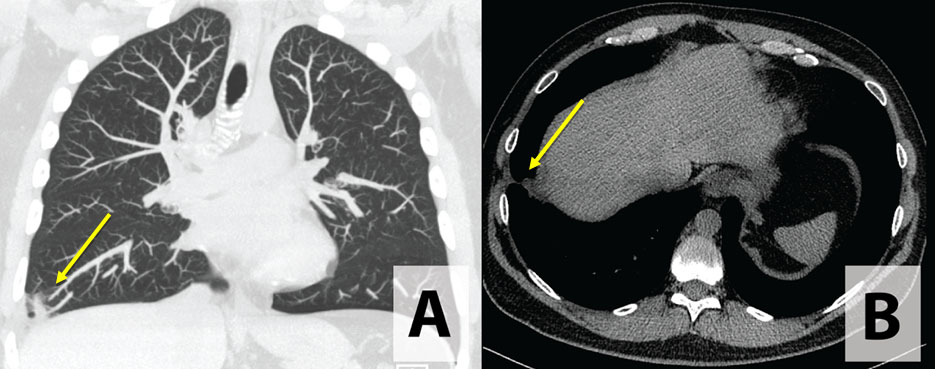

The patient was subsequently admitted, received intravenous (IV) ampicillin-sulbactam, and referred to Interventional Radiology and Pulmonology. Microbiologic workup included acid-fast bacilli (AFB) × 3, tuberculosis polymerase chain reaction (PCR) × 3, bacterial sputum culture, and other infectious workup including cryptococcal antigen, Histoplasma antigen, HIV, Coccidiosis, Aspergillus antigen, and quantiferon-gold. Pulmonary medicine felt the patient had necrotizing pneumonia secondary to recurrent aspiration events. No drainage was recommended, and instead the patient was discharged with an extended course of antibiotics with four weeks of amoxicillin/clavulanic acid (Augmentin®) and azithromycin for atypical coverage. Four weeks following discharge, repeat CT with contrast revealed interval resolution of the consolidation and abscess with mild scarring remaining (Figure 3).

Figure 3: CT chest without contrast demonstrating resolution of lung abscess with mild scarring: (A) coronal and (B) transverse.